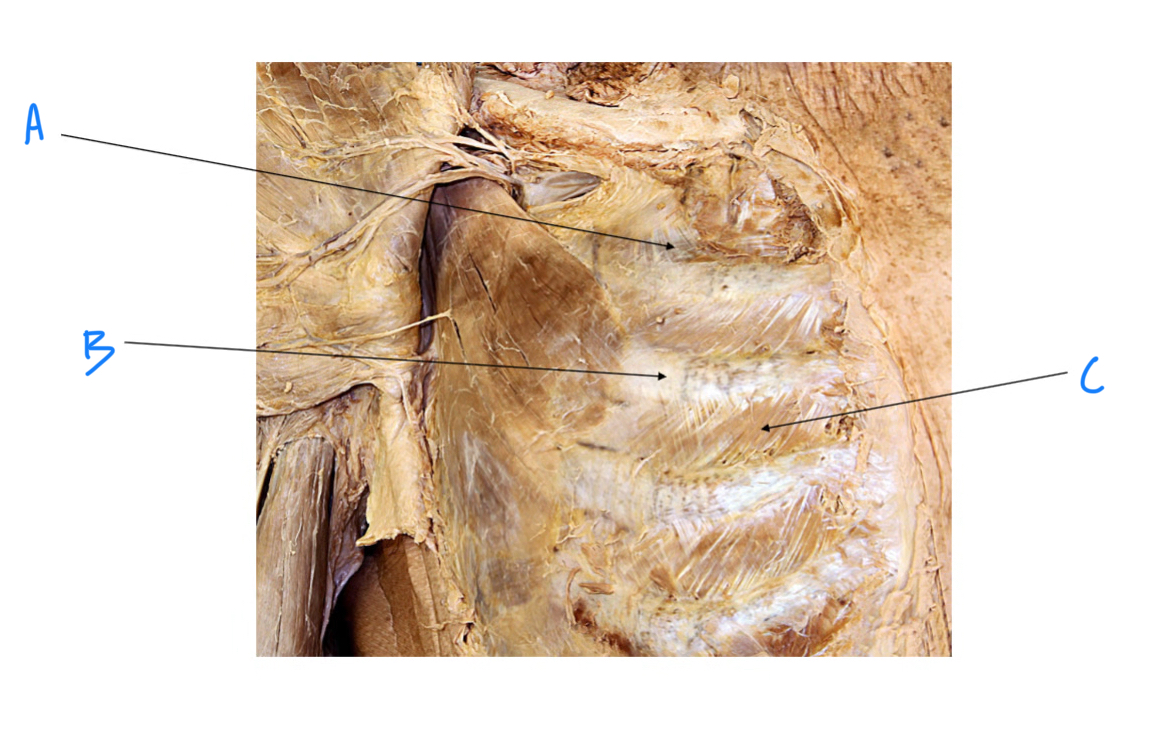

A. Identify structure

Transverse foramen; Vertebral a.

B. Identify structure; What goes through this feature?

Transverse process

C. Identify structure